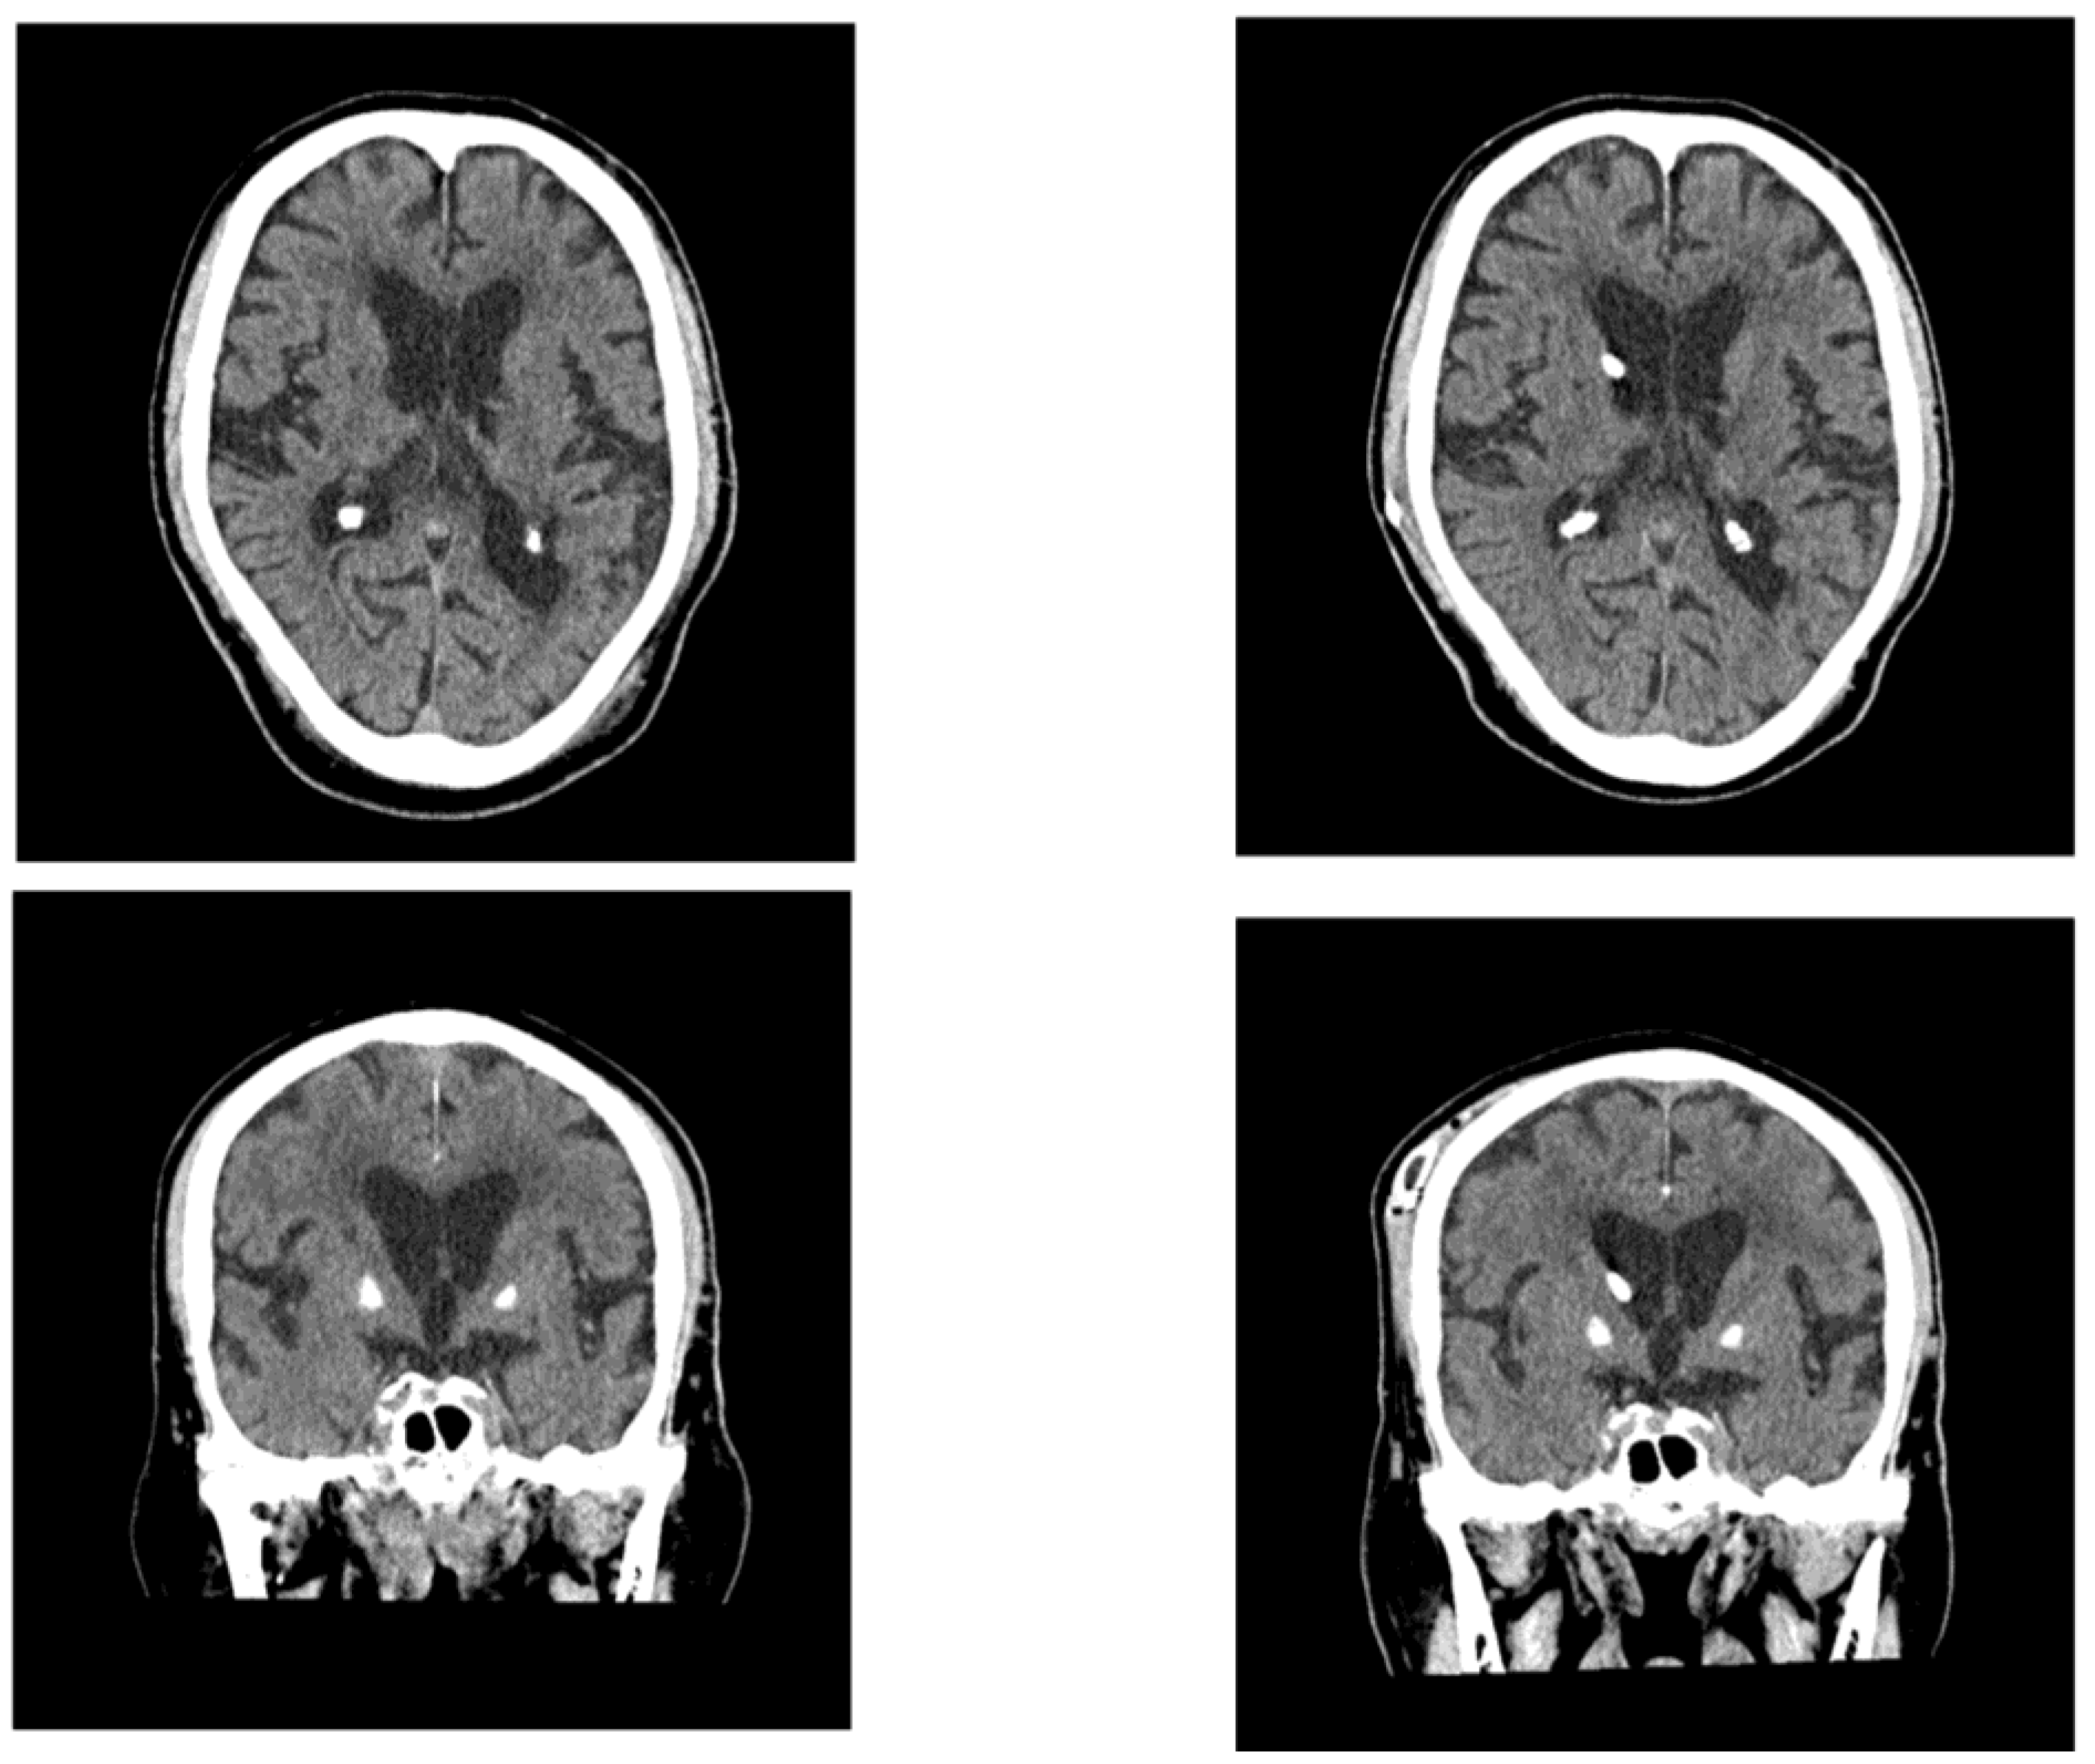

His body temperature on arrival was 37.5 °C. Laboratory tests revealed an increased inflammatory response and mild dehydration (Table 3). Blood cultures were obtained, and bacteremia with Stapylococcus haemolyticus was confirmed. Intravenous antibiotic therapy was promptly initiated. Brain MRI revealed enlarged lateral ventricles and features consistent with DESH. The patient’s Evans index was 0.38, and his corpus callosum angle was measured at < 90°, supporting the diagnosis of iNPH Acute cerebral infarction was identified in the corona radiata, indicating the coexistence of hydrocephalus and ischemic stroke (Figure 4).

Figure 4. MRI in Case 2 showing ventricular enlargement and acute cerebral infarction. The patient’s Evans index was 0.38, and indicating DESH. Acute infarction was observed in the left corona radiata.